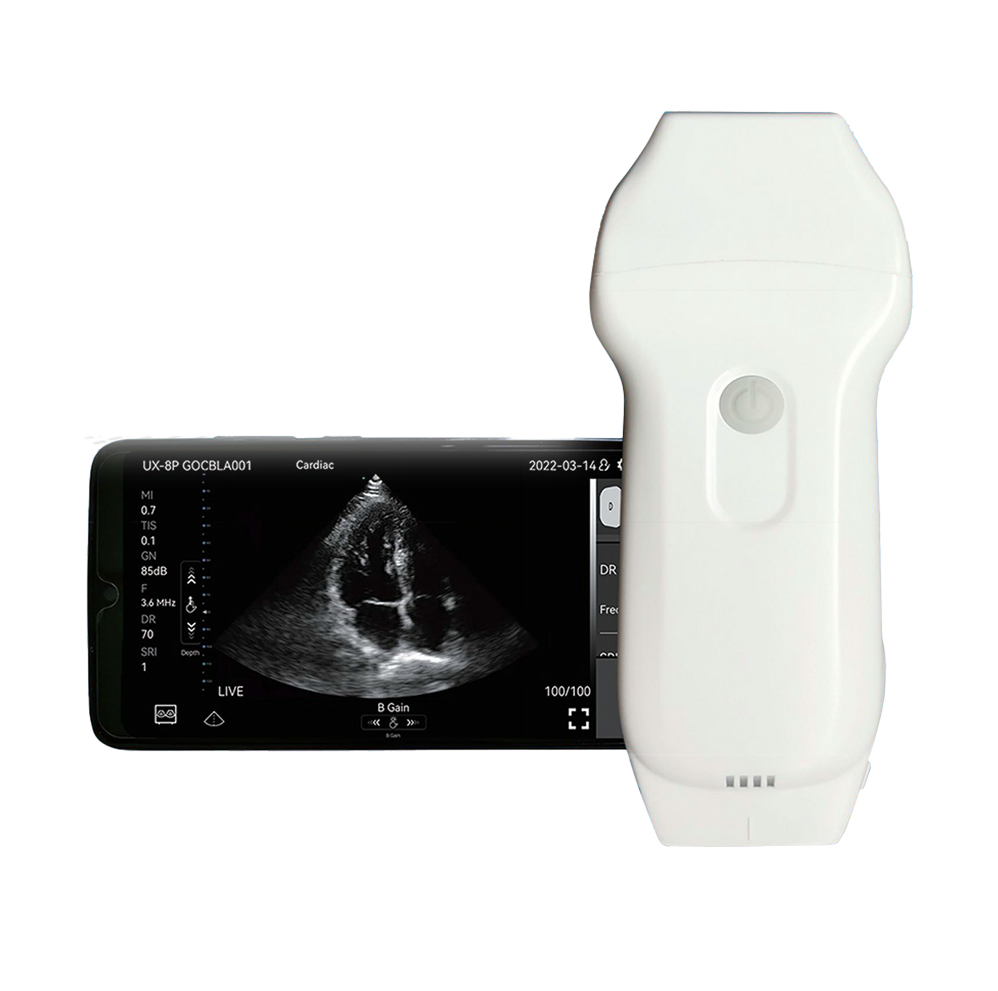

Ultrasound Scanner RK-4CPL

- remote interconnection, intelligent sharing

- waterproof disinfection, safe and reliable

- easy disinfection and remote diagnosis

Leave A MessageLive ChatProduct Introduction

Wireless ultrasound probe" is a miniultrasound scanner that without screen.We made the main unit condensed into a small circuit board builded-in theprobe, and showing image in smartphone/tablet through Wifi transferring.-Image transferring through internalwifi from probe, no need external Wifi signal.